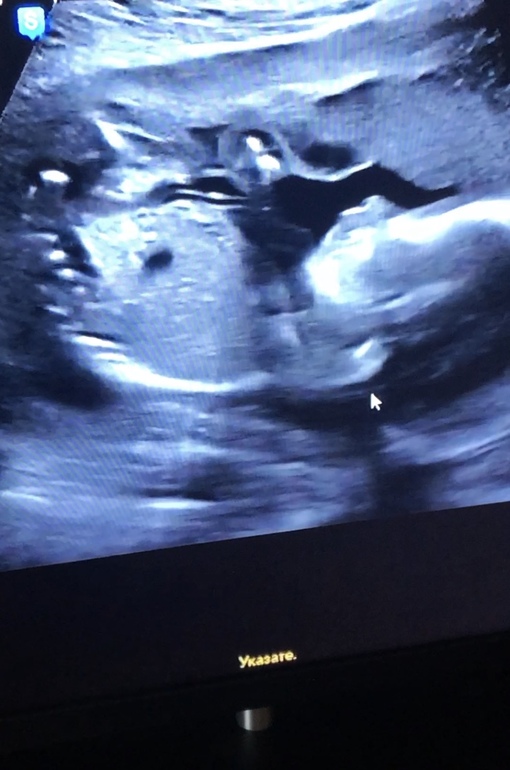

Экватор, 2й скрининг и фотопуз Тянет спина